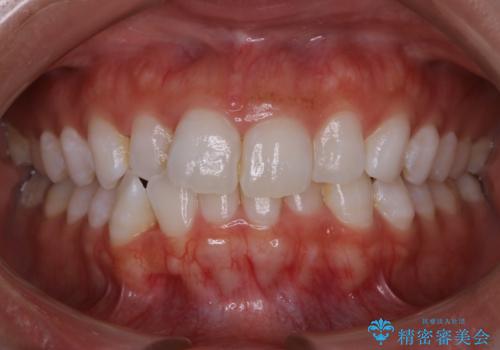

デコボコと変色した前歯 抜歯矯正と審美歯科治療